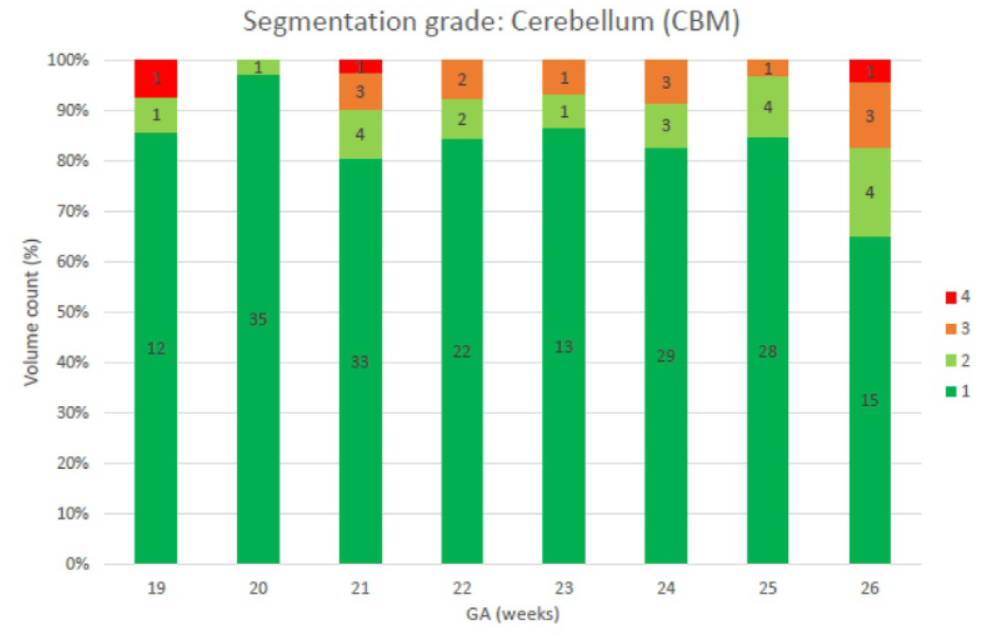

Clinical Grading of Artificial Intelligence‐Based 3D Fetal Brain Segmentations: A Cross‐Vendor Evaluation of Deep Learning in Fetal Neuroimaging

Prenatal Diagnosis

·

27 Feb 2026

·

doi:10.1002/pd.70103